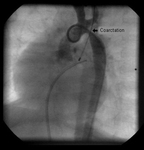

Angiography in the ascending aorta shows a focal area of narrowing after the left subclavian artery

From the personal collection of Jeffrey Gossett, MD, Children's Memorial Hospital, Northwestern University, Chicago; used with permission

After stent placement, the narrowed area is markedly improved